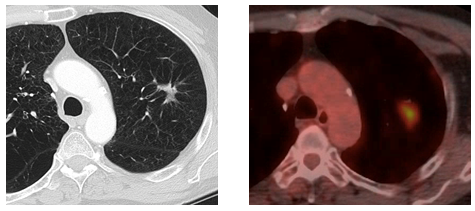

Figure D: 16 month axial CT and PET-CT scans concerning for local recurrence.

The patient failed to return at 12months post-treatment for follow up, and did not have his scan or visit until nearly 16months post-SBRT. This chest CT scan revealed an interval enlargement of the left upper lobe spiculated mass to a size of 2.7 x 5.5cm, with associated reorientation of the surrounding bronchovascular structures and dendritic extensions to the pleural surfaces and major fissure. Accompanying left upper lobe volume loss was also observed. Noteworthy high-risk features included craniocaudal growth and bulging margins. Figure 1 for evolving lesion imaging and treatment planning. A PET scan showed an increased SUVmax of 8.5 in the left upper lobe without additional metastatic disease. The patient underwent a CT-guided lung biopsy resulting in 8 samples being obtained prior to a complicating pneumothorax requiring hospitalization. Pathology was negative for cancer.